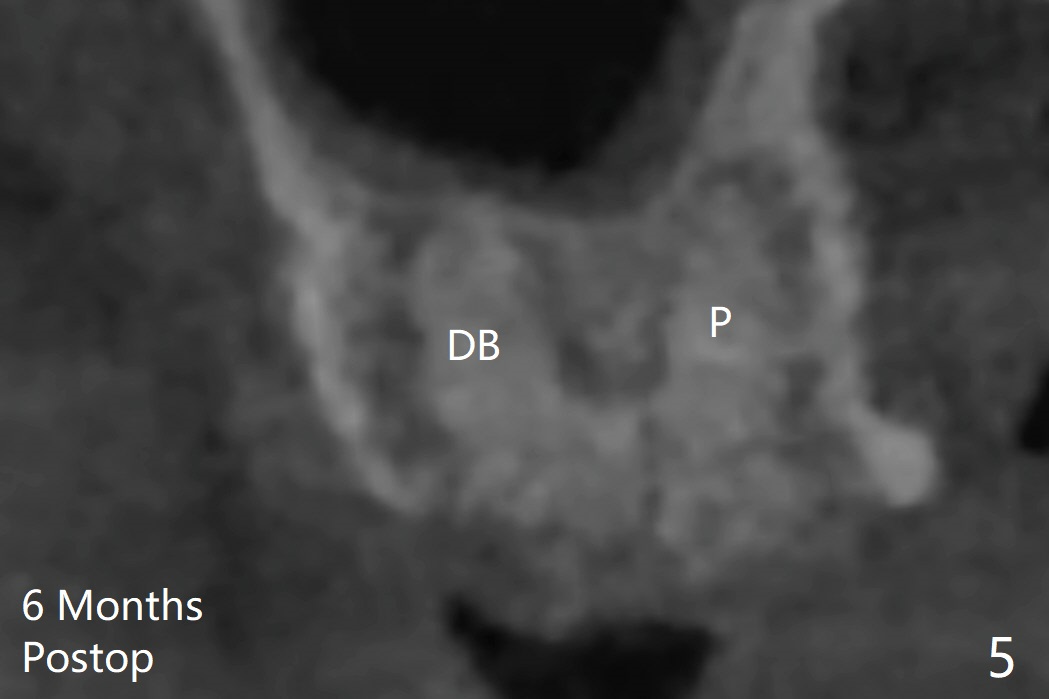

The dimension and density of the sockets will be measured 4-6 months later to determine whether rhPDGF-BB facilitates bone healing.